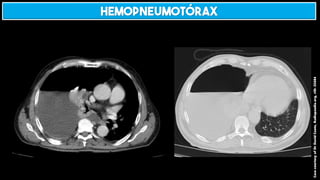

HEMOPNEUMOTÓRAX